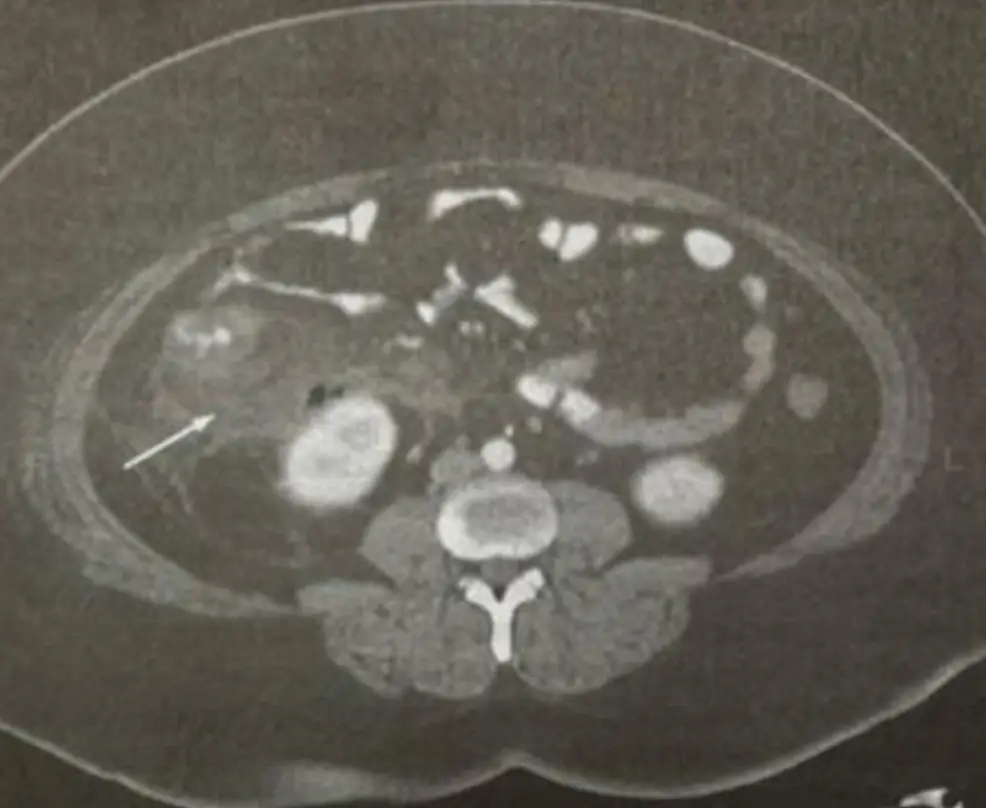

一位急性腹痛患者,在急診處接受腹部電腦斷層檢查,結果如圖,下列敘述,何者正確?

從所提供的腹部橫斷面電腦斷層(CT)可見,右下腹部出現一條直徑超過6毫米、壁明顯增厚、管腔內或周圍可見脂肪組織濃密度增加(fat stranding)的蠕蟲狀結構;這些變化正是acute appendicitis的典型影像學特徵。箭頭處指向之即為發炎的闌尾,周圍脂肪組織的條狀高密度改變與闌尾壁增厚合併,提示急性發炎反應。